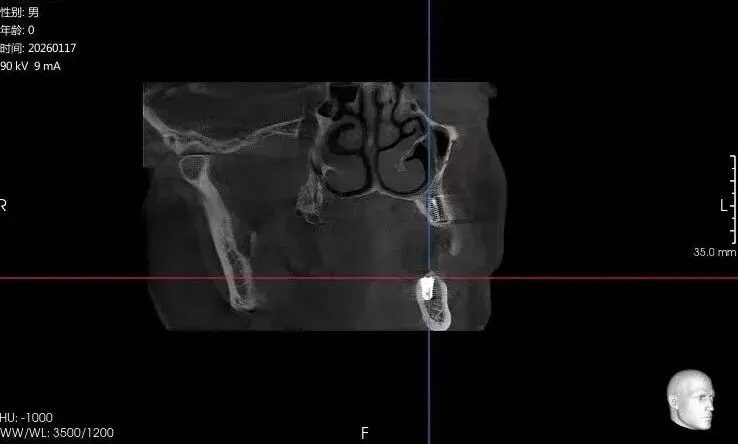

Case:患者罗某,男,种植一期术后因故未按时复诊,六年后来院复查,植入区CT影像如下:

图2:34CT矢状面

如图1、图2影像所示:植体上方有1-2mm厚的皮质骨覆盖,二期手术中应该去除阻碍覆盖螺丝脱位的牙槽骨,覆盖螺丝才易脱位。而在实际手术过程中,临床医生由于病情预估不到位或者操作经验不足,在未清除妨碍覆盖螺丝脱位的牙槽骨时强行反旋覆盖螺丝,导致覆盖螺丝六角冒丝,之后采用多种方法尝试取出未成功。本人多点执业救急,采用如下方法取出,未伤及植体,患者后期成功修复。